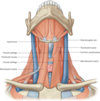

What are the muscles of the pharynx?

Superior, middle and inferior constrictors

Which 2 nerves form the pharyngeal plexus and what does it provide?

Glossopharyngeal and vagus nerves (strong sensory innervation)

Strong sensory innervation to the muscles of the pharynx

Which nerve controls the motor functions of the constrictors?

Vagus nerve (CN10) + accessory nerve (XI)

What is the action of swallowing?

Coordinated sequential contraction of superior, middle and inferior constrictors

Allows coordinated contraction of food bolus from mouth down to oesophagus